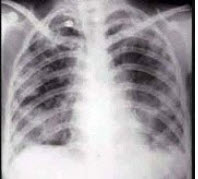

14、单项选择题

女性,32岁。1个月前诊断为系统性红斑狼疮,经激素治疗症状稍好转。近3天发热、咳嗽、咳少许粘痰。体检:肺呼吸音粗,无啰音。胸部CT示右下肺邻近胸膜处结节影。结节影呈晕轮征(ha1osign)(如图),最可能的诊断是()

A.血源性肺脓肿

B.金黄色葡萄球菌肺炎

C.肺曲菌球

D.原发性支气管肺癌

E.Wegener肉芽肿